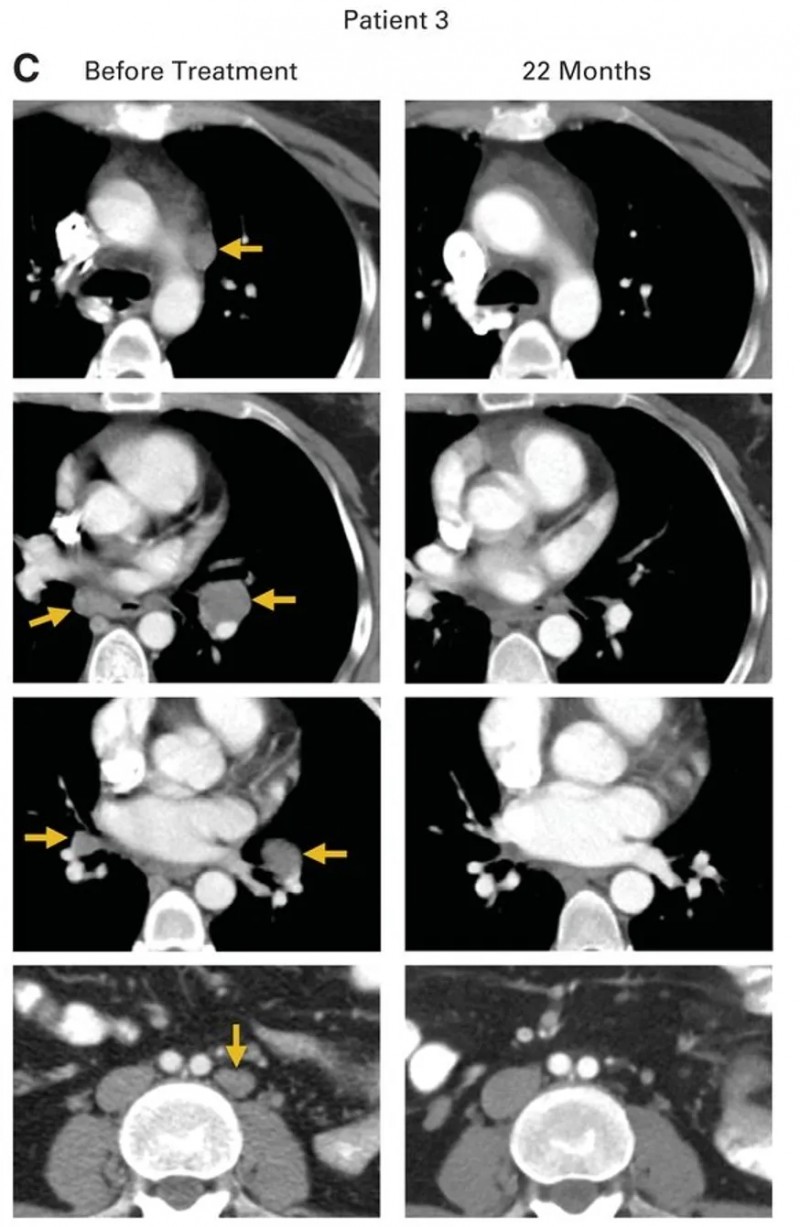

患者3(转移性鳞状细胞癌):经顺铂+长春新碱+博来霉素诱导治疗、吉西他滨+顺铂放化疗、拓扑替康+紫杉醇等多线治疗后,HPV-TIL治疗前肿瘤已进展至主动脉旁、双侧肺门、隆突下及髂骨等部位(详见下图C)。治疗后所有病灶完全消退,22个月时仍无疾病迹象。

▲图源“ASCO”,版权归原作者所有,如无意中侵犯了知识产权,请联系我们删除